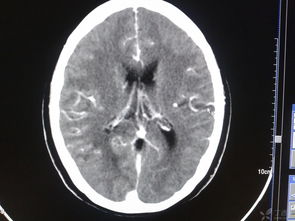

頭部損傷后常會(huì)發(fā)生繼發(fā)性顱內(nèi)損傷,其中最為嚴(yán)重的是顱內(nèi)血管破裂,形成顱內(nèi)血腫。

顱內(nèi)血腫形成后會(huì)使顱內(nèi)壓增高,使腦組織發(fā)生缺血、缺氧、水腫,顱內(nèi)壓力逐步增高,迫使部分腦組織發(fā)生移位而被擠進(jìn)顱內(nèi)生理孔道,形成危及生命的腦疝。 頭部受傷在天災(zāi)與人禍、戰(zhàn)爭與和平、生活與勞動(dòng)中均十分常見,其病情危急,變化無常,后果嚴(yán)重。

顱內(nèi)血腫形成后會(huì)使顱內(nèi)壓增高,使腦組織發(fā)生缺血、缺氧、水腫,顱內(nèi)壓力逐步增高,迫使部分腦組織發(fā)生移位而被擠進(jìn)顱內(nèi)生理孔道,形成危及生命的腦疝。由于傷者家屬甚至一般醫(yī)護(hù)工作者對顱內(nèi)血腫和腦疝的發(fā)生規(guī)律、臨床表現(xiàn)和危害性缺乏深刻了解,或因傷后過早進(jìn)行腦CT掃描(其時(shí)出血尚未發(fā)生,血腫尚未形成),對傷員觀察欠仔細(xì),延誤診斷和治療,結(jié)果發(fā)生傷員不幸死亡的悲劇。

此為家人警惕性高、觀察到病情變化及時(shí)復(fù)診、醫(yī)生及時(shí)診斷并手術(shù)成功的典型病例。 目前診斷顱內(nèi)血腫最可靠最快捷的手段是CT掃描,它能在數(shù)分鐘內(nèi)清晰地顯示出血部位、血腫大小和伴隨的其他情況。

顱內(nèi)血腫若能及時(shí)診斷和手術(shù),病人是可以完全康復(fù)的。